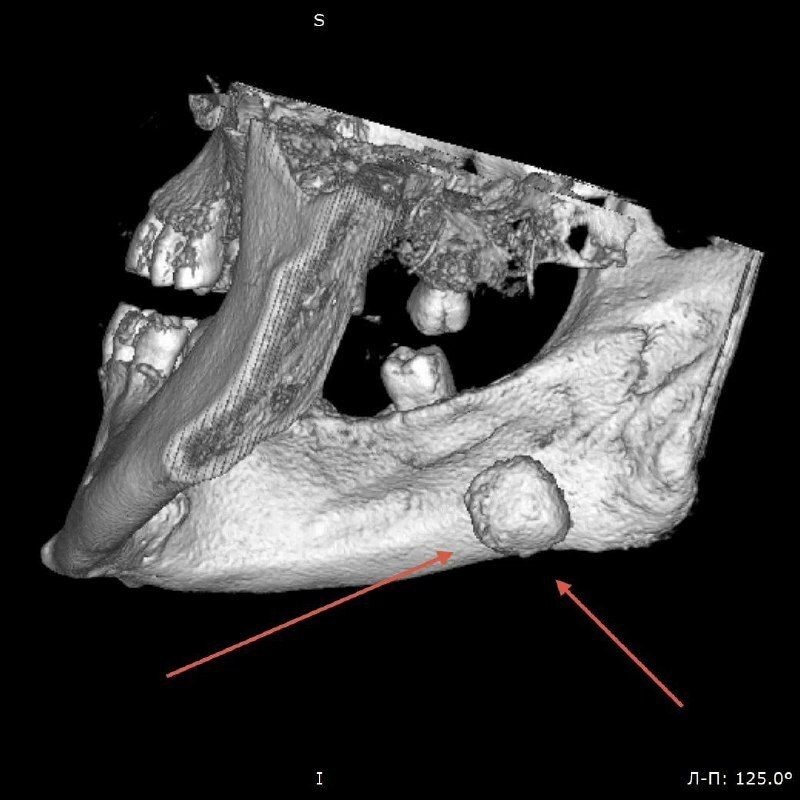

Бу хакта медицина учреждениесе матбугат хезмәтендә хәбәр иттеләр. Хирурглар Приморьеда яшәүче 38 яшьлек кешенең төкерек бизеннән диаметры 2 см дан артык булган ташны алдырганнар.

Пациент "төкерек‑таш авыруы" диагнозы белән килгән — төкерек агымы бозыла торган сирәк авыру.

Ташның зур булуына карамастан, табиблар төкерек бизен саклап кала алган. Гадәттә мондый очракларда аны тулысынча алып ташларга туры килә.